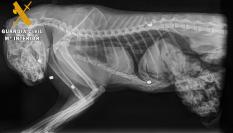

Esta acción motivó la intervención policial que, ante el estado del animal, requirió la presencia de los servicios veterinarios de la clínica Les Campes, que trasladaron al can al hospital veterinario, en donde ingresó ya en estado de coma con braquicardia, parada respiratoria, estado de shock e hipertemia por un golpe de calor sufrido durante el desplazamiento, en un día con la temperatura muy alta, de 32 grados.

El animal presentaba lesiones abrasivas en la zona abdominal, escroto, extremidades anteriores y posteriores en la zona de la rodilla. Pese a las maniobras de reanimación, el animal falleció.